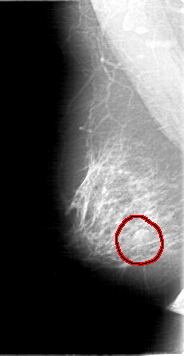

D_4067_1.RIGHT_MLO

RIGHT_CC LINES 4681 PIXELS_PER_LINE 2206 BITS_PER_PIXEL 12 RESOLUTION 43.5 OVERLAY

RIGHT_MLO LINES 5326 PIXELS_PER_LINE 2746 BITS_PER_PIXEL 12 RESOLUTION 43.5 OVERLAY

FILE: D_4067_1.RIGHT_MLO.OVERLAY

TOTAL_ABNORMALITIES 1

ABNORMALITY 1

LESION_TYPE MASS SHAPE OVAL MARGINS MICROLOBULATED

ASSESSMENT 0

SUBTLETY 4

PATHOLOGY BENIGN

TOTAL_OUTLINES 1

FILE: D_4067_1.RIGHT_CC.OVERLAY